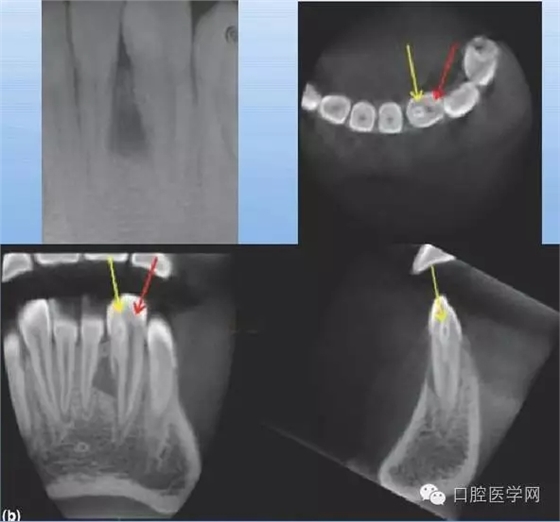

牙中牙

X線表現(xiàn):舌側(cè)窩陷入過(guò)深,形似一小牙包于牙髓中。